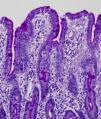

Light microscopy shows varying degrees of atrophy of the brush border microvilli, no significant signs of an inflammatory response and a normal or slightly increased density of the crypts. In healthy subjects, alkaline phosphatase27 and PAS staining only stain the brush border of the enterocyte, while in patients with MVID the border is either not stained or is stained unevenly and there is an accumulation of PAS-positive materials in the apical cytoplasm of enterocytes (Fig. 1). This can also be observed by means of CD1028 (Fig. 2) and carcinoembryonic antigen immunostaining.29 The three key ultrastructural findings include the reduction, absence and/or disorganization of microvilli in mature enterocytes; the accumulation in the apical cytoplasm, and especially of crypt cells, of secretory granules; and the characteristic intracytoplasmic inclusion bodies lined with microvilli (Fig. 3). However, it is not always easy to make a histopathological diagnosis of MVID due to the existence of variants, different clinical manifestations and even a small percentage of patients in whom the typical inclusion bodies cannot be detected. In 1994 Raafat et al.30 described three children with microvillous dystrophy, a condition they considered a clinicopathologic variant of MVID that has since been addressed by other authors.24 This ultrastructural lesion was observed in patient 1 (Fig. 4).